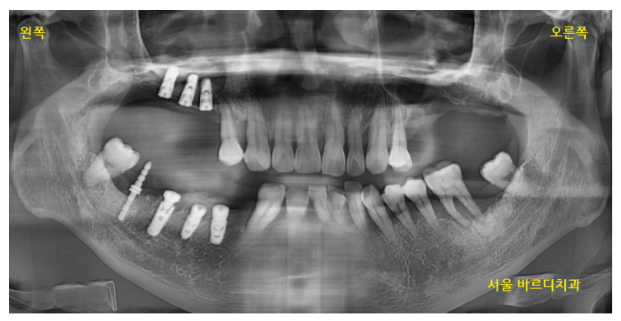

230612

환자분처럼 양쪽 어금니가 다 없고

임플란트 뼈이식을 많이 해야할경우

안전하게 오른쪽 왼쪽 나눠서

임플란트 수술을 진행합니다.

환자분은 왼쪽이 많이 불편하시다 하셔서

왼쪽부터 수술을 진행하였습니다.

(환자분의 요구사항이 1순위 반영사항입니다)